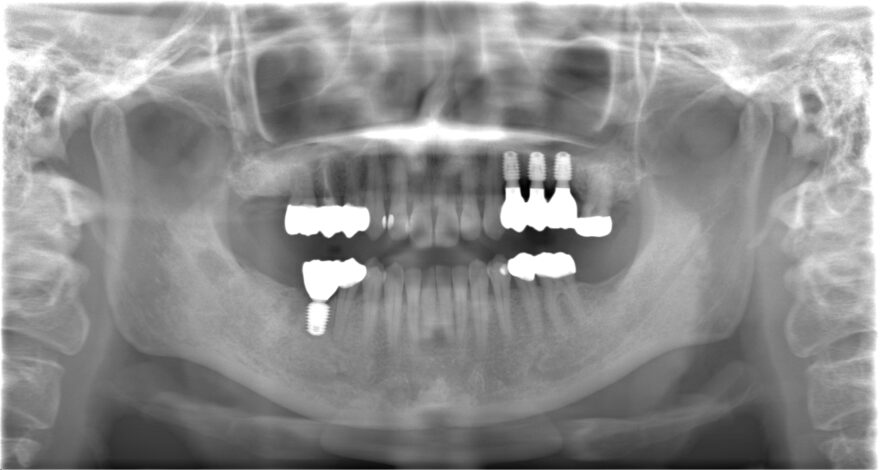

初診時のレントゲン写真

治療後のレントゲン写真

インプラントと噛み合う右下に2本、左上に3本のセラミックを被せています。

インプラント治療と全体的な噛み合わせ治療を組み合わせることで、歪んだ噛み合わせのバランスを補正しました。